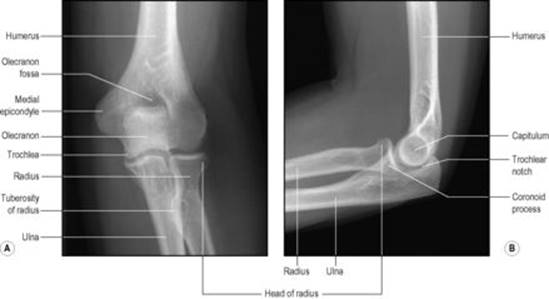

This is a synovial joint of the hinge variety between the lower end of the humerus and the upper ends of radius and ulna (Fig. 2.23). It communicates with the proximal radioulnar joint.

Radiographs of the elbow joint: A anteroposterior projection; B lateral projection.

(Provided by Dr R. Sinnatamby, Addenbrooke's Hospital, Cambridge.)

The lower end of the humerus has the prominent conjunction of capitulum and trochlea (Fig. 2.24). The capitulum is a portion of a sphere which articulates with the upper surface of the head of the radius. It projects forwards and downwards, and is not visible on the posterior aspect of the humerus (Fig. 2.55). In contrast the trochlea, which lies medial, is a grooved surface that extends around the lower end of the humerus to the posterior surface of the bone and articulates with the trochlear notch of the ulna. The groove of the trochlea is limited medially by a sharp ridge that extends further distally. Laterally a blunter ridge blends with the articular surface of the capitulum more proximally. Thus a tilt is produced at the lower end of the humerus that accounts in part for the carrying angle of the elbow. Fossae immediately above the capitulum and trochlea receive the head of the radius and coronoid process of the ulna, respectively, in full flexion; posteriorly a deep fossa receives the olecranon in full extension.